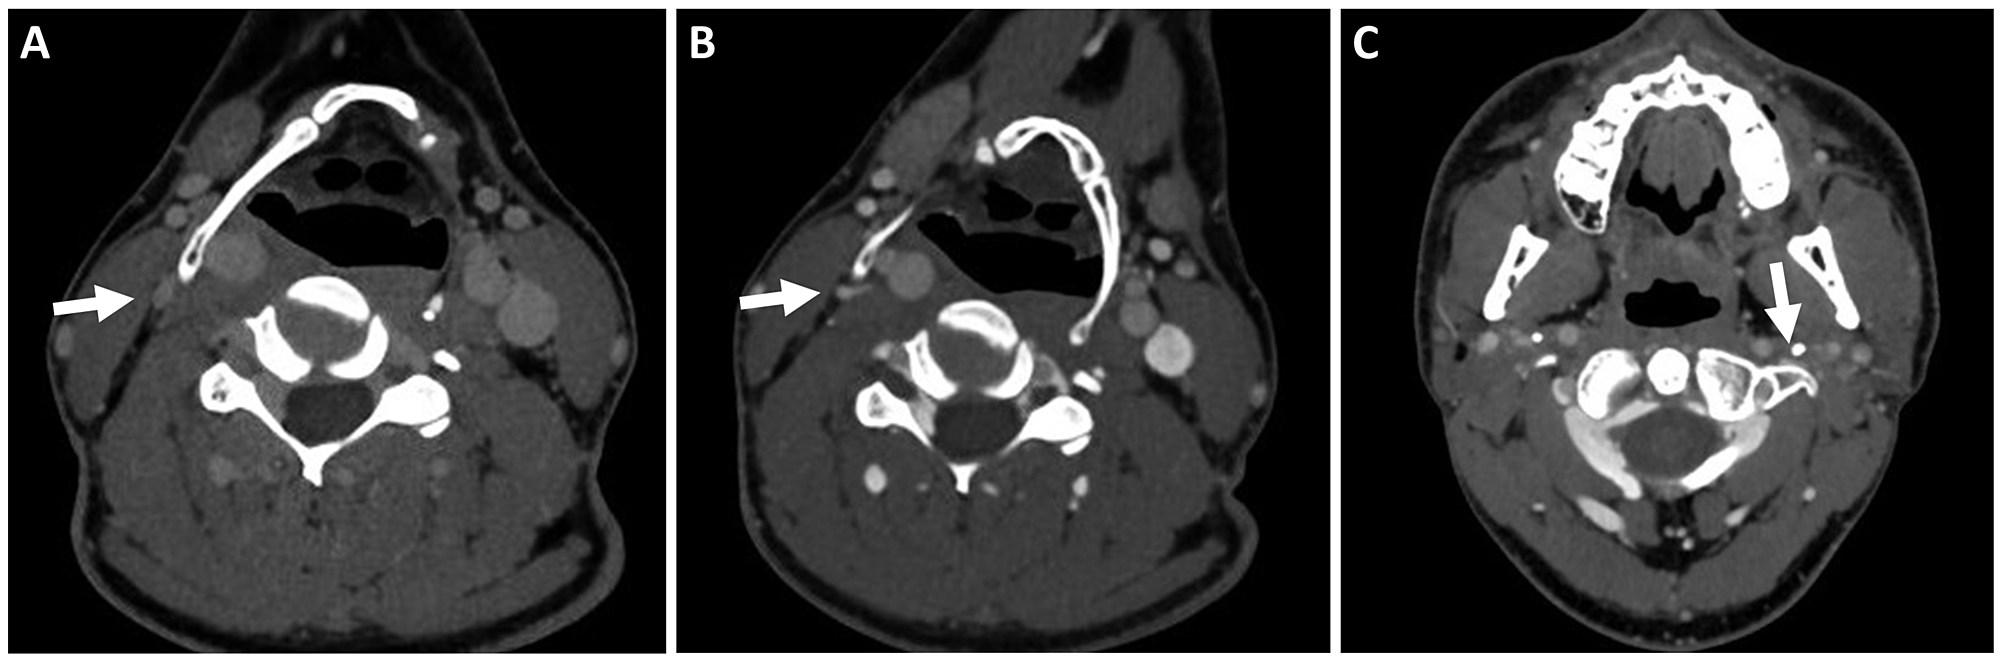

Cureus Dynamic Internal Jugular Vein Compression by Hypertrophic Hyoid Bone Management and What Causes Jugular Vein Compression One of the main causes of jugular vein compression is thought to be craniocervical instability (cci), a condition caused by the misalignment of the upper neck bones c1 and c2 that can lead to. The jugular veins on either side of your neck carry blood back to your. Internal jugular vein compression can cause intracranial hypertension causing many symptoms like. What Causes Jugular Vein Compression.

Figure 4 from Dynamic Internal Jugular Vein Compression by Hypertrophic Hyoid Bone Management What Causes Jugular Vein Compression Typically, there are three pairs of jugular. This happens because blood is not returning to the heart properly, and it may occur along with symptoms. Surrounded by blood vessels (internal carotid artery and internal jugular vein) and nerve networks and near the c2 vertebrae. Jugular vein distention (jvd) occurs when neck veins bulge out because of pressure. One of the. What Causes Jugular Vein Compression.